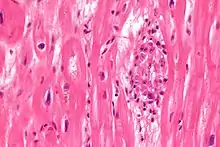

| Aschoff bodies are microscopic structures seen in patient with rheumatic fever | |

In medicine, Aschoff bodies are nodules found in the hearts of individuals with rheumatic fever. They result from inflammation in the heart muscle and are characteristic of rheumatic heart disease. These nodules were discovered independently by Ludwig Aschoff and Paul Rudolf Geipel, and for this reason they are occasionally called Aschoff–Geipel bodies.

Microscopically, Aschoff bodies are areas of inflammation of the connective tissue of the heart, or focal interstitial inflammation. Fully developed Aschoff bodies are granulomatous structures consisting of fibrinoid change, lymphocytic infiltration, occasional plasma cells, and characteristically abnormal macrophages surrounding necrotic centres. Some of these macrophages may fuse to form multinucleated giant cells. Others may become Anitschkow cells or "caterpillar cells," so named because of the appearance of their chromatin.

They are pathognomic foci of fibrinoid necrosis found in many sites, most often the myocardium. Initially they are surrounded by lymphocytes, macrophages, and a few plasma cells, but they are slowly replaced by a fibrous scar. Aschoff bodies are found in all the three layers of the heart, least chance in the pericardium.

The Aschoff nodules are foci of T lymphocytes, occasional plasma cells, and activated macrophages (Anitschkow cells) pathognomonic of rheumatic fever. These macrophages have abundant cytoplasm and central round nuclei in which chromatin condenses into a central, slender, wavy ribbon, the reason why they are sometimes called "caterpillar cells". They are especially found in the vicinity of small blood vessels in the myocardium and endocardium and occasionally in the pericardium, and also the adventitia of the proximal part of the aorta. Lesions similar to the Aschoff nodules may also be found in extra-cardiac tissues.